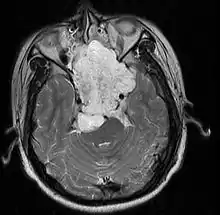

- Skull base:

- May be intracranial or extracranial, with mass effect symptoms depending on location

- Headaches and/or facial pain are common

- Pituitary insufficiency, hemianopsia/diplopia, cranial nerve deficits, nasal stuffiness.

Skull Base

- Hannover; 2007 (Germany) PMID 17695386 -- "Chordomas of the skull base: surgical management and outcome." (Samii A, J Neurosurg. 2007 Aug;107(2):319-24.)

- Retrospective. 49 patients. Transethmoidal approach 36%, pterional 23%, retrosigmoid 23%.

- Outcome: GTR 49%, subtotal resection 51%. Initial surgery GTR 78%. 5-year OS 65%, 10-year OS 39%

- Toxicity: New neurological deficit 12%

- Conclusion: Chordoma cannot be regarded as surgically curable tumors, given the 5- and 10-year OS